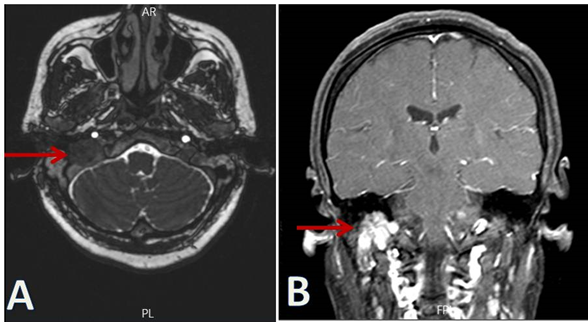

The findings on computerized tomography (CT) scan and magnetic resonance imaging (MRI) suggested a glomus jugulare tumor with destruction of the jugular foramen (Figure 1). CT scan of abdomen showed no evidence of mass lesion and alaboratory tests also showed a normal level of noradrenaline (in plasma and urine) and urinary vanillylmandelic acid (VMA). Seven days prior to surgery, preoperative embolization of tumor vessels was performed. Preoperatively, haemoglobin was 10.8 g/dl. After consultation with a cardiologist and endocrinologist, she was transported to operating room. Prior to induction of anesthesia, standard monitoring including pulse oximeter, ECG and after tracheal intubation End-tidal carbon dioxide (ET CO2) monitors applied. The vital signs were as follows:  blood pressure of 132/76 mmHg, heart rate of 92 beats/min with sinus regular rhythm and oxygen saturation (SPO2) was 98 on room air. After placing two large 16-G intravenous catheters and an arterial line in the left radial artery for close haemodynamic monitoring and administration of fluids and vasopressors if needed intraoperatively, midazolam 2 mg and fentanyl 1.5μg/kg were injected. The anesthesia was induced with intravenous propofol 2mg/kg, lignocaine 1 mg/kg and cisatracurium 0.2mg/kg. Anesthesia was maintained uneventfully with isoflurane 0.2%-0.4% in oxygen and fentanyl and cisatracurium. The patient also received propofol (50-75µg/min) and dexmedetomidine (0.1 - 0.15 µg /kg/hour) infusions during surgery. The extracranial and intracranial tumors were resected by an otolaryngologist and neurosurgeon, respectively.  Intraoperatively, the patient received one blood unit. In the end of surgery, the neuromuscular blockade was reversed successfully with neostigmine and atropine. When she was fully awake, then, she extubated in the operative room after 13 hours and 40 minutes of surgery. The patient required no hemodynamic support during the procedure. Ultimately, she was transported in a good condition to intensive care unit (ICU). She also had no need of tracheal reintubation or using any inotropes or vasopressors in the ICU and ward.

Figure 1 Preoperative MRI images. Arrows show erosion of the right jugular foramen in temporal bone axial T2 (A) and coronal T1 contrast enhanced views (B), respectively.